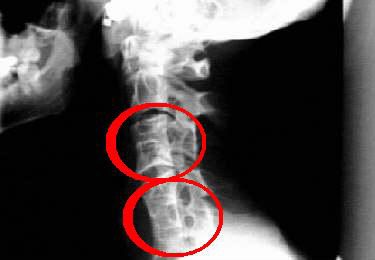

Но шишка на шее может быть признаком и заболеваний эндокринной системы, поэтому важно правильно поставить диагноз в этом случае. Диагностируется остеохондроз на основании клинической картины и рентгенографии

Все эти проявления могут усиливаться при выполнении любых движений, что доставляет сильный дискомфорт пациенту. При обнаружении у себя на шее шишки при остеохондрозе шейного отдела лечение следует начинать с посещения мануального терапевта или невропатолога. Также может потребоваться сделать рентген шишки на шейном позвонке для более точной диагностики заболевания.

Шишка на шее: фото (рентген).